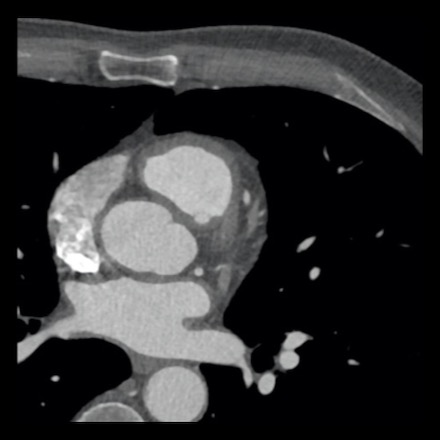

case 1 – CAD-RADS 2/P1

First, scroll through the scan.

Not all images are included. Some images without any abnormalities are skipped

from the series.

How would you describe the findings on the coronary CTA?

The findings are:

- Agatston score of

this patient was 14 (P1). Please, also note the calcification of the aortic valve. - Some partially

calcified and calcified plaques are present in the LAD with mild stenosis

(25-49%). - Calcified-plaque in

the LCX causing minimal stenosis (<25%). - Non-calcified

plaque in the distal RCA causing minimal stenosis (<25%). - This patient classifies

as CAD-RADS 2/P1, which means no further workup is needed.